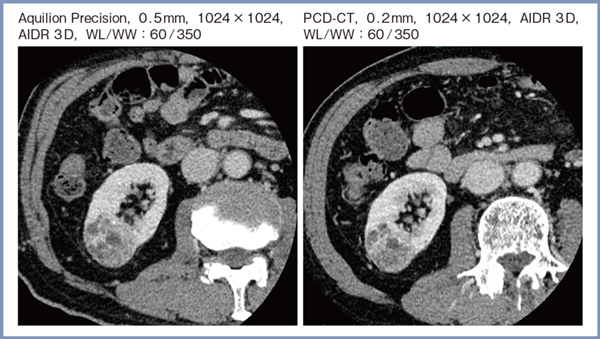

右腎腫瘍の症例にて,Deep Learning Reconstruction(DLR)の「Advanced intelligent Clear-IQ Engine(AiCE)」を適用したAquilion Precisionの画像と,AIDR 3Dを適用したPCD-CTの画像(共に1024×1024マトリックス,スライス厚5mm)を比較したところ,ほぼ同等の画質が得られた。また,AIDR 3Dを適用したAquilion Precision(スライス厚0.5mm)およびPCD-CT(スライス厚0.2mm)のthin slice画像を比較したところ,解像度はほぼ同等であった(図6)。なお,同じthin slice画像で,Aquilion PrecisionにはAiCEを適用したところ,ノイズが低減し良好な画質が得られた。ここからわかるとおり,DLRの画質改善効果は高く,PCD-CTにおいても有効性が期待される。

図6 右腎腫瘍におけるAquilion PrecisionとPCD-CTのthin slice画像の比較